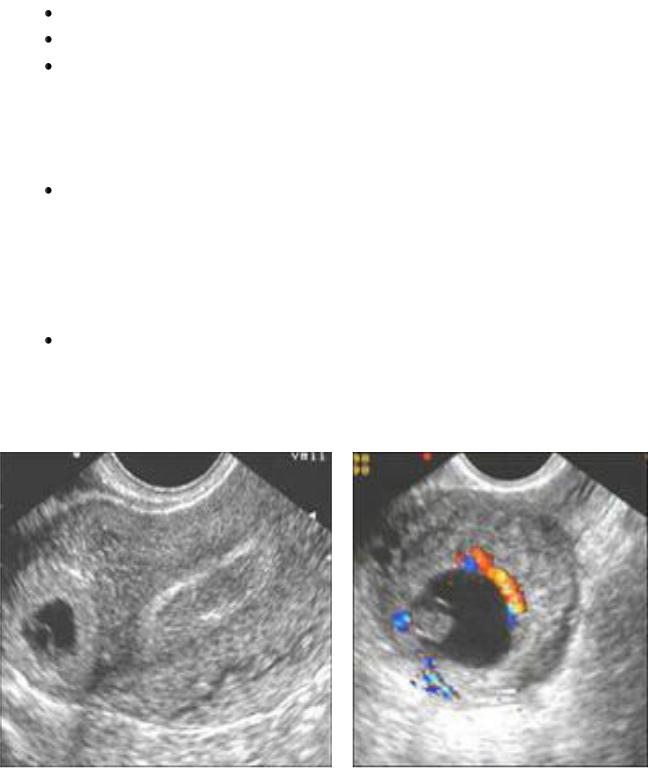

Лапароскопия: кровь в брюшной полости, синюшно-красная утолщенная маточная труба, гематосальпингс, перитубарная гематома, возможно, разрыв трубы (рис.3, 4).

Рис. 3, 4. Лапароскопическая картина трубной беременности.

Лапароскопия является наилучшим доступом для проведения операции по поводу эктопической беременности. Доступ определяется с учетом состояния больной (рис.5).

Левосторонняя трубная беременность

Рис. 5. Лапароскопическая картина трубной беременности.